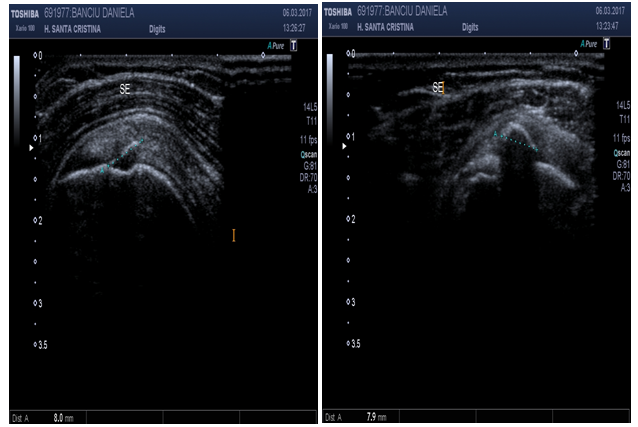

Superior Acromioclavicular (AC) joint (Figure 2)

Patient position: Patient is seated, arm at side, elbow flexed with palm up (supination).

Probe position: Long axis over distal clavicle.

Scan of structures: AC joint is a synovial articulation delimited by the end of clavicle, usually higher than the acromion.

Abnormal findings: Increased fluid in joint capsule, also called as “Geyser sign” might indicate inflammation, recent trauma or rheumatologic issues. Narrowed joint space and osteophytes may denote Osteoarthritis, or degenerative joint disease.17,18

Figure 2 Sonoanatomy of the acromioclavicular joint.